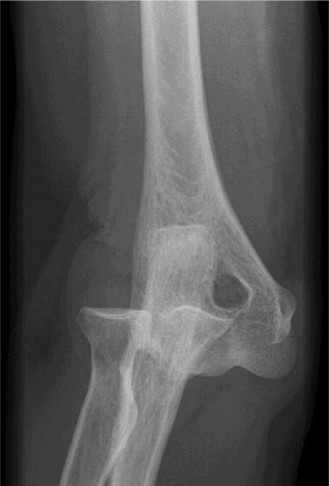

Anteroposterior (AP) and lateral radiographs of the right elbow were obtained.

Initial AP and Lateral Radiographs:

These views clearly demonstrated a posterior dislocation of the ulnohumeral joint. The olecranon was positioned posterior to the distal humerus. Crucially, the radiographs revealed associated fractures.

- There was a comminuted fracture of the radial head (Mason Type III).

- A significant coronoid process fracture was identified, involving approximately 50% of the coronoid height, consistent with a Regan-Morrey Type II fracture.

- Evidence of avulsion fractures from the medial epicondyle (consistent with MCL injury) and lateral epicondyle (consistent with LCL complex injury) were also noted, indicating extensive soft tissue disruption.

(Representative initial lateral radiograph demonstrating posterior elbow dislocation with associated coronoid and radial head fractures.)

(Representative initial AP radiograph illustrating the elbow dislocation and comminuted radial head fracture.)

Given these findings, a diagnosis of a terrible triad injury of the elbow was made.